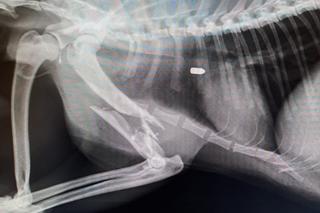

"Cleo, została znaleziona w okolicach Piasecznika (gm. Choszczno) w stanie rozkładu" - informują przyrodnicy. - "Po zbadaniu ciała w jej szczątkach zabezpieczono kilka śrucin".